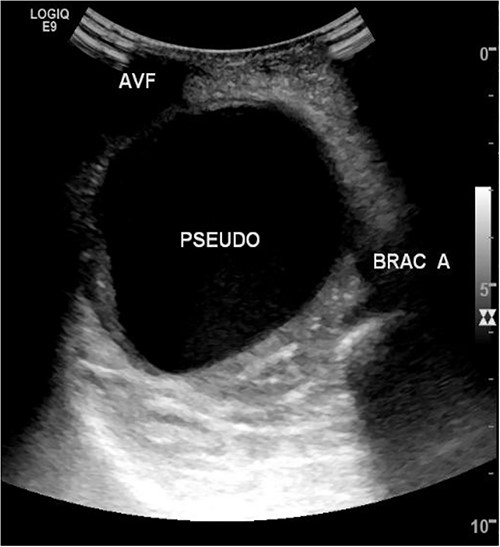

A 78-year-old female with history of coronary artery disease, hypertension, hyperlipidemia, and end-stage renal disease on hemodialysis through a right brachio-basilic arteriovenous fistula presented to the hospital with prolonged bleeding after dialysis. She was not taking any antiplatelet or anticoagulation medication. She had previously undergone stenting of the proximal basilic vein due to venous stenosis. Right upper extremity fistulogram identified recurrent basilic vein stenosis within the previous stents. Balloon venoplasty was performed via 6 Fr sheath. Repeat fistulogram demonstrated persistent stenosis of the proximal basilic vein and so the sheath was upsized for Viabahn stent placement. During the sheath exchange, there was some contrast extravasation around the sheath access site (Fig. 1), which resolved with a longer 7 Fr sheath. Completion fistulogram did not show residual stenosis and the patient was discharged the following day. The patient continued to use her fistula for hemodialysis during the next 2 months.

Fistulogram demonstrating contrast extravasation around the sheath access site.

She then re-presented 2 months later with gradually increasing right upper extremity edema with a palpable thrill in the arteriovenous fistula. Duplex identified a large hematoma with patency of the fistula (Fig. 2). A tunneled dialysis catheter was placed to allow the swelling and hematoma to resolve. After medical optimization, the patient consented for operative intervention with the intention to evacuate the hematoma. There was noted to instead be a 20 × 35 cm PSA of the brachial artery (Fig. 3). The median nerve was identified and preserved. After proximal and distal control, the patient was heparinized, and the brachial artery PSA was decompressed with evacuation of large mural thrombi (Fig. 4). This artery segment was resected, and patch angioplasty was performed (Fig. 5). The fistula was ligated, and the distal remnant was preserved. Radial and ulnar pulses were palpable. The patient recovered well postoperatively.